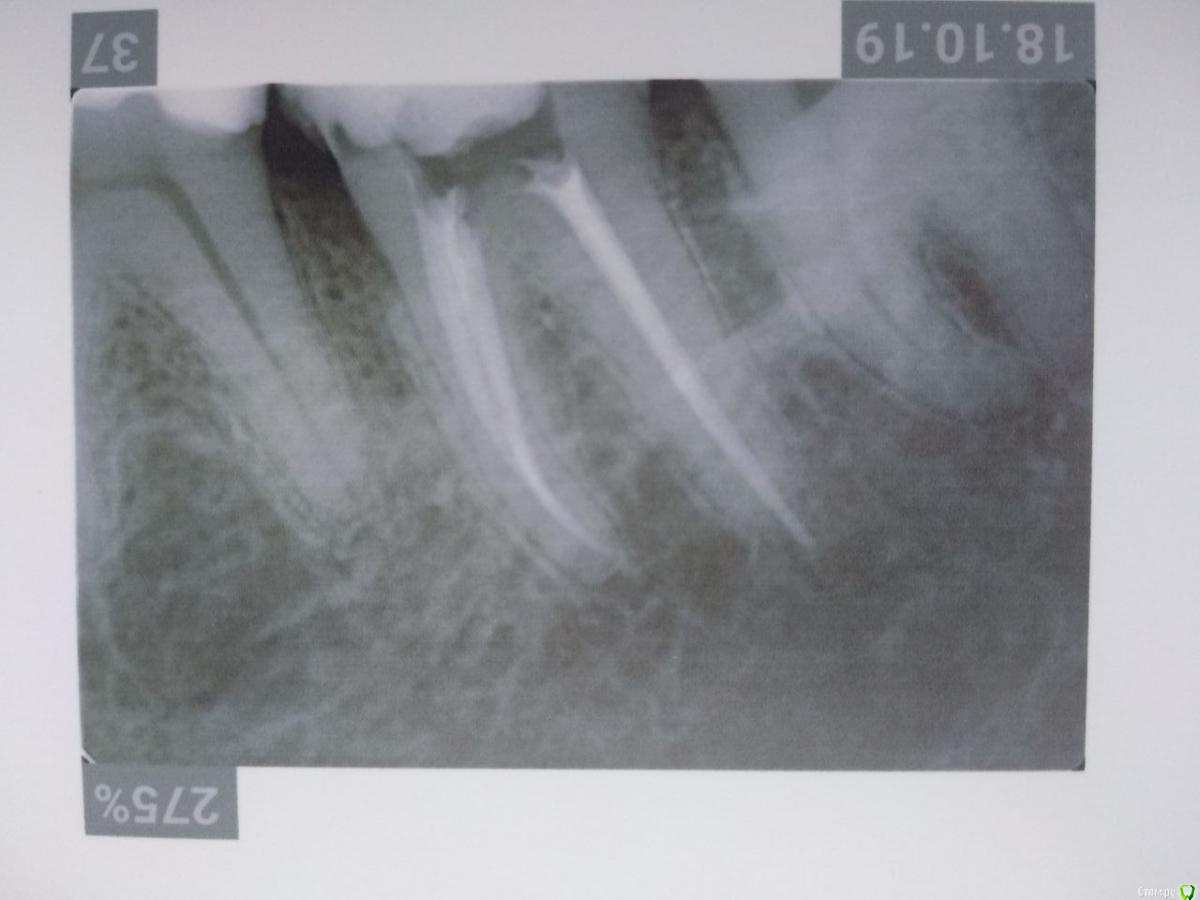

Здравствуйте! Откололся кусок зуба. 8 октября сделали КЛКТ (3Д снимок всех зубов). Вскрыли зуб, была проведена девитализация. Поставили диагноз: хронический фиброзный пульпит 37 зуба. 18 октября было проведено первичное лечение 3-х канального зуба эндомотором с использованием микроскопа и системы коффердам. Все каналы были запломбированы гуттаперчивыми штифтами на силлере методом латеральной конденсации Adseal, внутрь заложена ватка и поставлена временная пломба дентин-паста. 29 октября ортопед №1 посмотрел прицельный снимок (см. снимок зуба 2) и сам зуб, пломбу не снимал. Озвучил, что у меня низкая высота зуба, мне нужно установить культевую кобальт-хромовую вкладку и сверху покрыть металлокерамической коронкой зуб. Также сказал, что циркониевая вкладка мне не подходит из-за высоты. Однако, поскольку ортопед №1 уходил на обучение, мне было предложено обратиться в другую клинику к другому ортопеду. 1 ноября ортопед №2 посмотрев мой зуб без снимка заявил, что у меня сохранились три стенки у зуба и мне надо просто закрыть пломбой этой зуб. Поскольку ортопед №2 предложил диаметрально противоположное лечение зуба, то я решил обратиться в третью клинику. Ортопед №3 посмотрев снимок моего зуба, сам зуб, в том числе внутри (снял мою временную пломбу из дентина), заявил, что у меня низкая высота зуба и мне нельзя ставить культевую вкладку и коронку. И было предложено сделать вкладку из пресс керамики overlay. Также когда удалили временную пломбу у меня увидели кариес на этом зубе. В конце приема мне взамен снятой пломбы установили временную пломбу парасепт.

Покажите снимок до лечения, по вашему фото точно сказать есть ли кариес в этом зубе нельзя, возможно есть, рентгеновский снимок нижнего зуба, а вы выкладываете вверх корнями, поправте  это, и думаю стоит перелечить,  как минимум дистальный канал(корень), по вашему снимку определяется выведение гуттаперчи за пределы корня это не по стандарту, выведение силлера допускается. У форума нет задачи определять, кто и кого разводит на деньги! мы помогаем людям в их сложных клинических ситуациях. В случае приведения пломбировки корней к приемлемому виду, я бы закончил его лечение фиксацией пресскерамической вкладкой, покрывать депульпированные зубы жевательной группы пломбами крайне не желательно.

Спасибо за ответ. Перевернул снимок. Прицельного снимка до лечения не делали, только КЛКТ. Не знаю насколько подойдет снимок из КЛКТ, но прикрепил. Я правильно Вас понял, что мне пролечили плохо каналы под микроскопом, в частности дистальный канал, тк гуттаперча вышла за пределы корня? Мне нужно повторно перелечить этот канал под микроскопом?